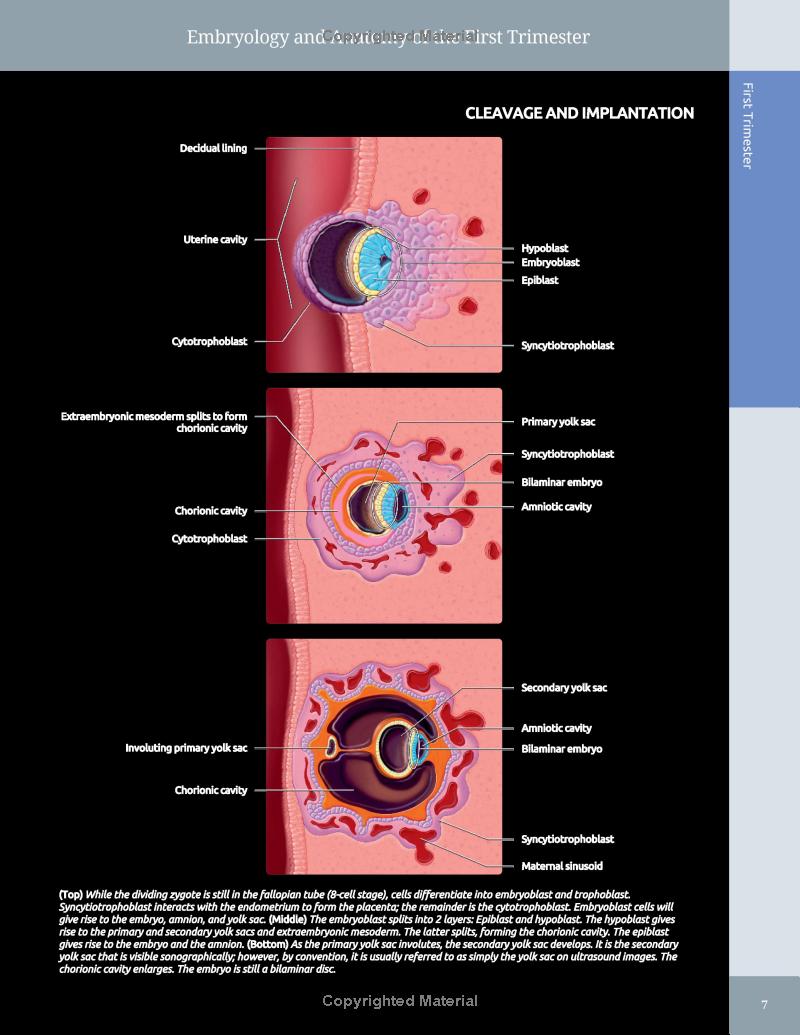

The newest edition of Diagnostic Imaging: Obstetrics provides fetal imagers with world-class content and instruction on the latest methodologies in this rapidly changing field. Featuring approximately 260 diagnoses highlighting the most recent information, references, and images, this title serves as a practical, highly formatted guide that’s well suited for today’s busy fetal imaging centers. Enhanced chapters on embryology, new reference tables, updated patient management guidelines, and much more ensure readers are current with the knowledge required for competent clinical practice.

- Features expanded embryology chapters delineating normal developmental anatomy

- Richly colored graphics and fully annotated images highlight the most important diagnostic possibilities